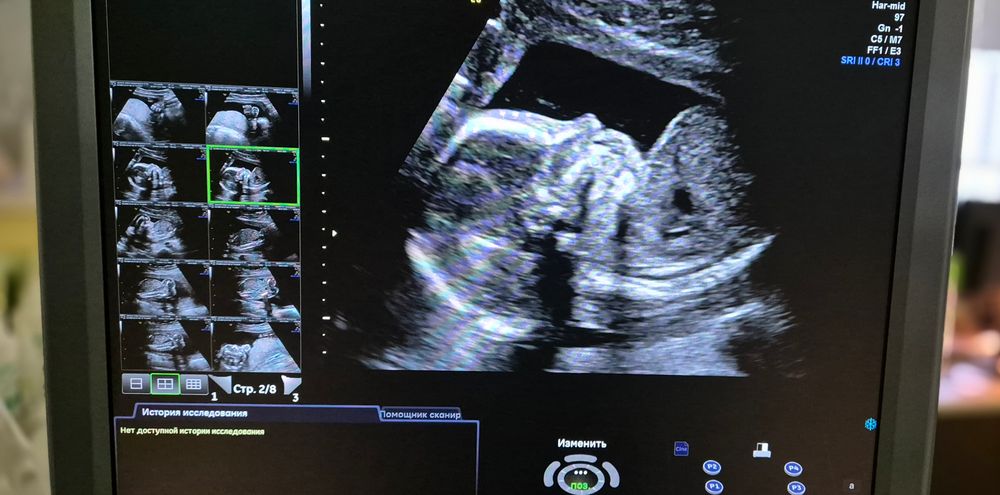

II скрининг ✅

Второй скрининг был не такой волнительный, как первый, но всё же переживала. Думаю, это нормально)) Сказали, что всё хорошо 🕺 Сын показал попу, писю, покрасовался главными местами. Ну как без этого, мужик же 😂😂я счастлива!!! И ведь столько времени уже ношу его под сердцем - сегодня ещё больше осознание пришло, что скоро в нашем доме появится он 👶Долгожданный зайка! Мы с папой тебя уже так любим ❤️эх, аж слеза накатила 😄